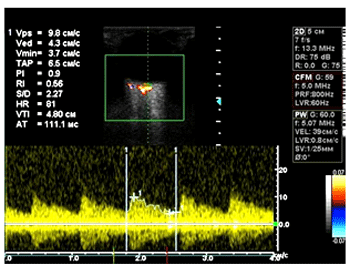

Оценка показателей кровотока в ГА, ЦАС и ЗКЦА производилась при помощи ультразвуковой допплерографии (УЗДГ) на многоцелевой диагностической системе Vivid 3 (General Electric, Израиль) с исполь-зованием линейного датчика с частотой 13,3 МГц в импульсном режиме. Гемодинамические характеристики определяли в ГА на отрезке до образования ее дуги над зрительным нервом (на расстоянии 10,1 – 14,9 мм от заднего полюса глазного яблока), в ЦАС – 1,5 – 3,0 мм от заднего полюса в пределах диска зрительного нерва, в ЗКЦА – 0,7 – 0,33 мм от заднего полюса глазного яблока в непосредственной близости от зрительного нерва. Количественная оценка глазного кровотока включала следую-щие амплитудные параметры и индексы допплерограммы:

С целью изучения характера кровотока в сосудах глаза и орбиты мы проанализировали параметры ультразвуковой допплерографии в ГА, ЦАС и ЗКЦА.

Для оценки полученных результатов пациенты были разделены на группы в зависимости от длины переднезадней оси глаза (ПЗО). В I группу вошли пациенты с ПЗО – 23,37 ± 0,52мм, преимущественно с эмметропической рефракцией и миопией слабой степени. Во II группу были включены пациенты с миопией средней и высокой степени и средней величиной ПЗО – 26,41 ± 0,67мм. Различий в показателях кровотока в ГА выявлено не было. Показатели гемодинамики в ЦАС представлены на рис. 2.

Рис. 2. Характер кровотока в ЦАС при разной рефракции у пациентов с ПВХРД

Из диаграммы следует, что у пациентов II группы в ЦАС отмечалось статистически значимое снижение V max, V min и V med. Большее изменение минимальной и средней скоростей обусловило достоверное повышение индексов резистентности и пульсаторного. На парных глазах выявлено снижение систолической и средней скорости кровотока. У пациентов I группы показатели кровотока в ЦАС не отличались от нормы.

В ЗКЦА нами диагностировано снижение всех скоростных параметров в группах пациентов с ПЗО – 23,37 ± 0,52мм и на парном глазу без дистрофии относительно контроля (V max 0,127 ± 0,01м/с, V min 0,049 ± 0,013м/с, V med 0,08 ± 0,013м/с, RI 0,63 ± 0,01, PI 1,006 ± 0,04). Так, в I исследуемой группе систолическая скорость кровотока составила 0,01 ± 0,02м/с, диастолическая – 0,037 ± 0,015м/с, а усредненная по времени – 0,062 0,017м/с; на парных «здоровых» глазах – 0,1 ± 0,03; 0,031 ± 0,015 и 0,059 ± 0,018м/с соответственно. В группе парных глаз Vmed и Vmin изменены более значительно, что отразилось в статистически значимом повышении RI и PI (0,68 ± 0,11 и 1,196± 0,35). Показатели второй исследуемой группы не отличались от контрольной.

Рис. 3. Спектр кровотока в ГА при осложненном характере течения ПВХРД